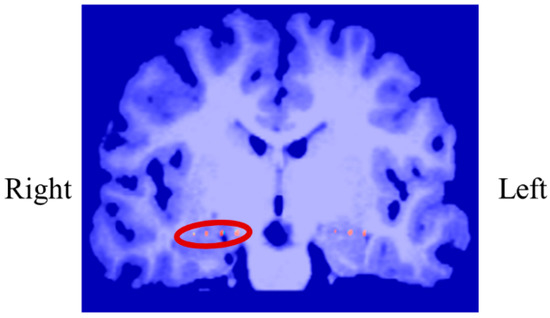

In P02, subdural electrodes (Unique Medical, Tokyo, Japan) were implanted in the left MTL, covering the hippocampus. Four platinum electrodes (1.5 mm in diameter) were longitudinally placed at 5 mm intervals (centre to centre) along the left parahippocampal gyrus, and iEEG was measured and used for NF (Figure 12). A reference electrode placed on the dural side of the right temporal lobe was used for P02.